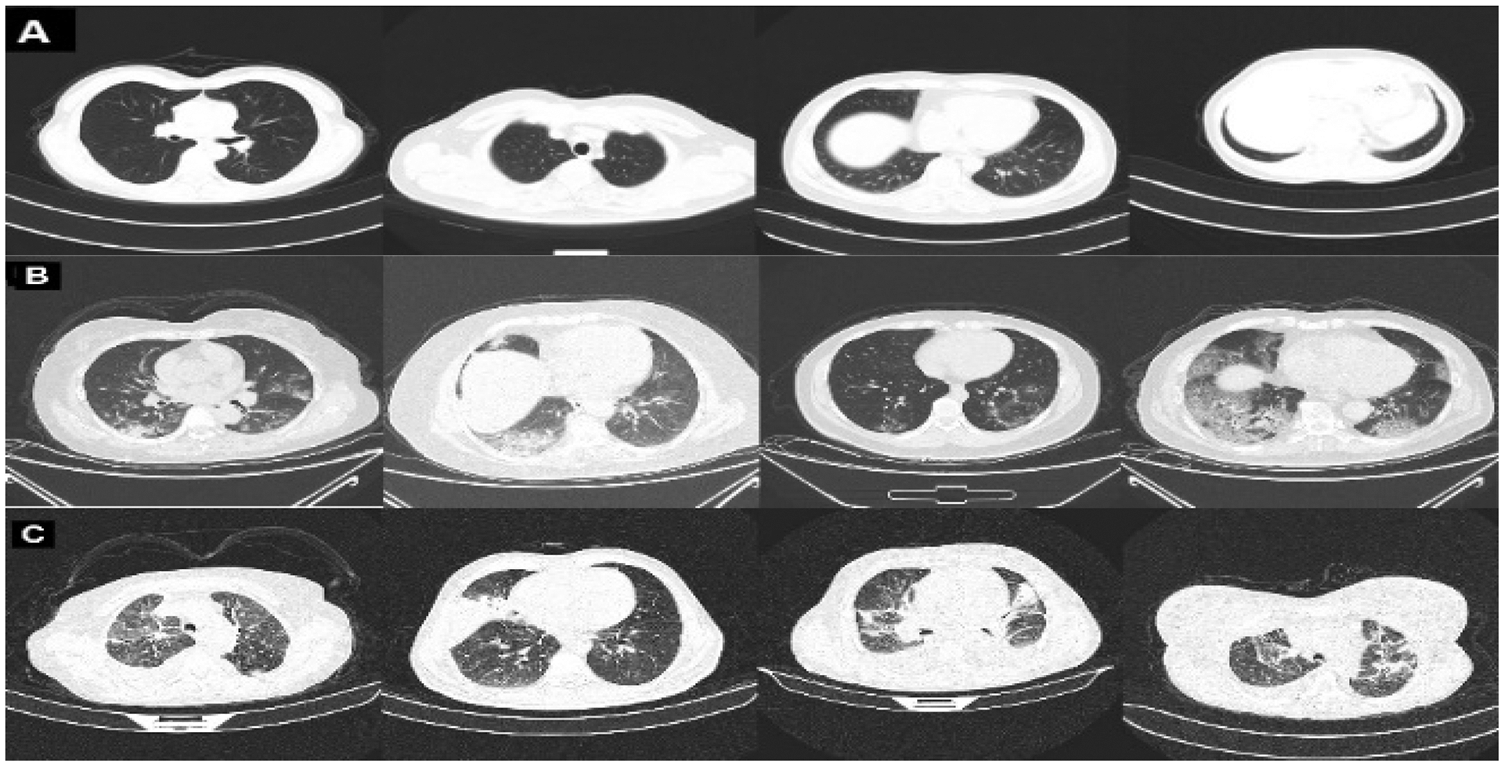

The COVID-CT dataset [29] contains two groups of images. The first group consists of (349) images for COVID-19 patients, while the second consists of (397) images for a non-COVID-19 lung infection. Two datasets are also used to increase data. COVID_DATASET [30] comprises of three classes COVID-19 (719 images), Normal (2495) and pneumonia (1825). Finally, the SARS-CoV-2 CT dataset [31] contains two classes: 1252 COVID-19 CT images for infected patients by COVID-19 and 1230 non-COVID19 CT images, which contains another pulmonary disease. Since we aim to build a dataset that contains three classes as mentioned above, the non-COVID images from the last two datasets are excluded because they may contain a different variety of pulmonary diseases, Fig. 2 shows samples of our dataset.

Figure 2: Representative samples from our dataset representing A: normal, B: COVID-19, and C: pneumonia